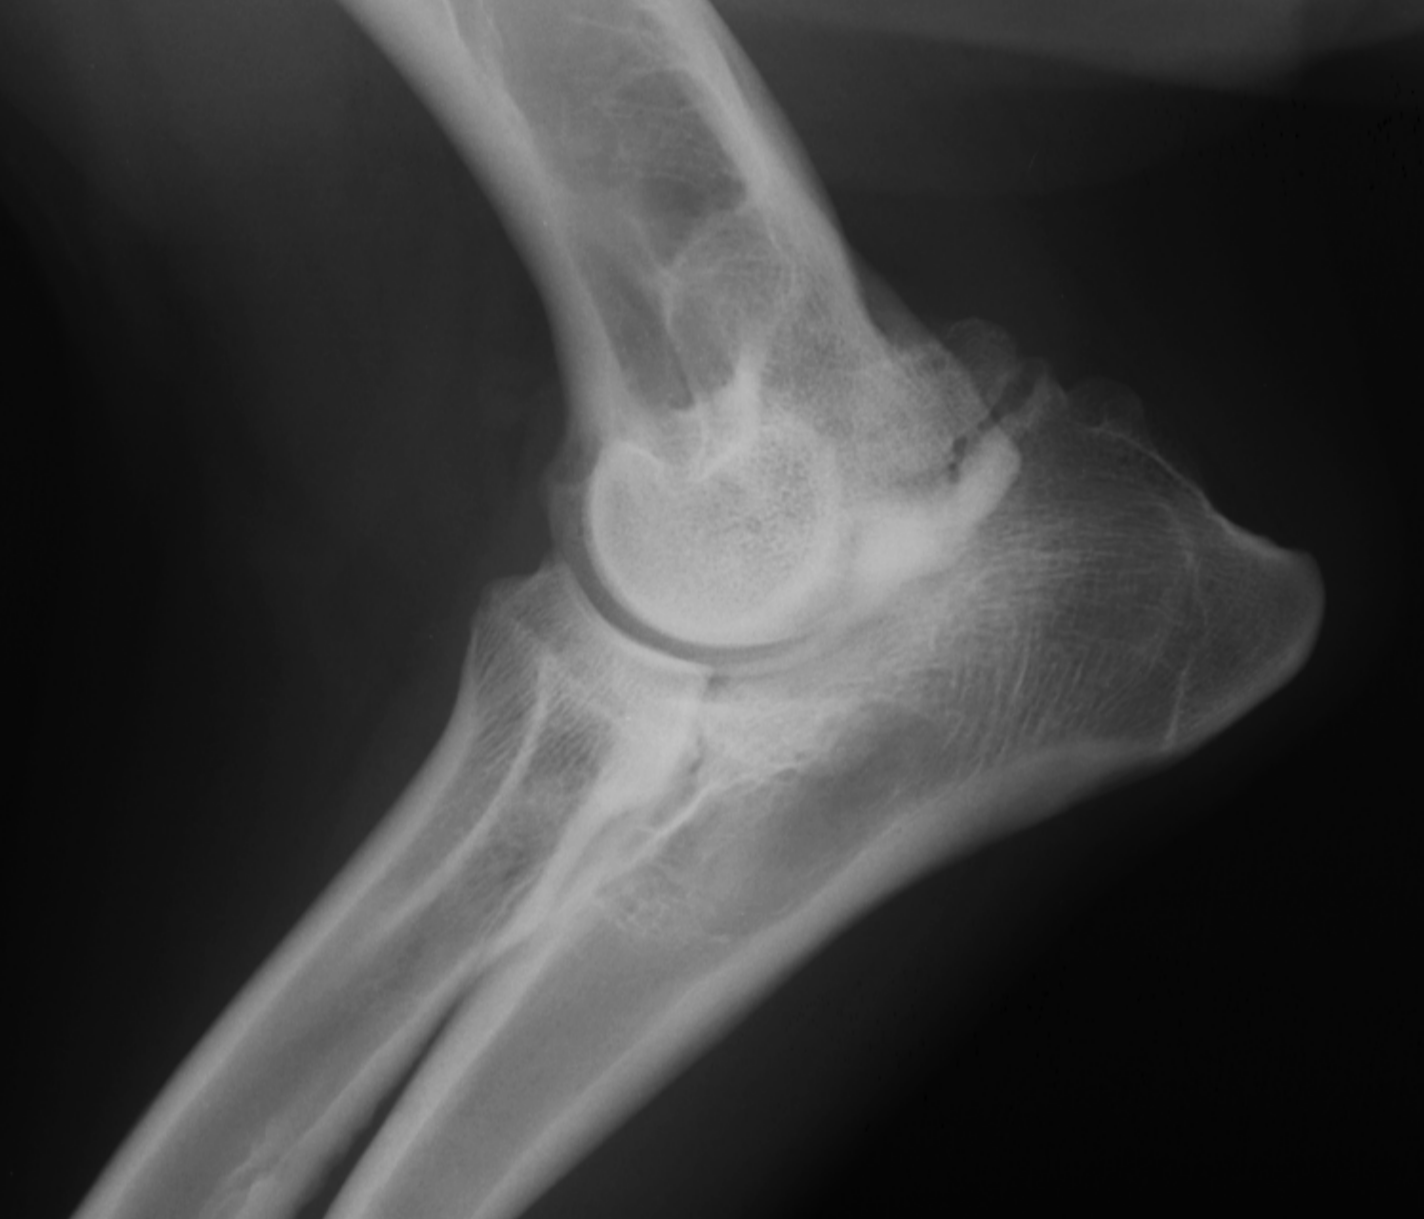

which OCD lesions are these in the dog

A = cd humerus

B = medial humeral condyle (elbow)

C = medial trochlear ridge (ankle)

D =lateral femoral condyle (knee)

4 OCD lesion locations in the dog

cd humerus

medial humeral condyle (elbow)

lateral femoral condyle (knee)

medial trochlear ridge (ankle) - worst prognosis